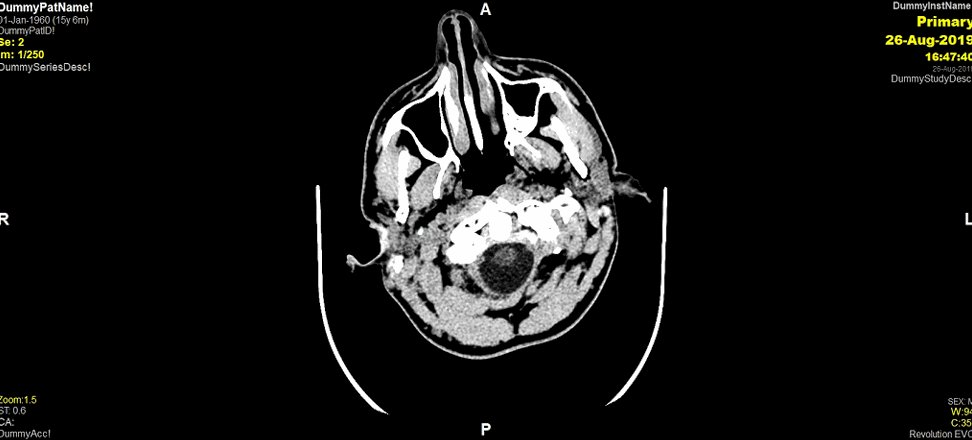

6. Given his dangerous mechanism of injury, and the loss of consciousness, a CT head is performed. What does it show?

7. Indeed! The CTH shows a L sided EDH. You’ll see from this scan there is no effacement of the ventricles nor midline shift. Because of the findings, you refer him to the on-call neurosurgeon. They are in a hospital 45 mins away. What would you ask if you were that neurosurgeon?

31. Good work guys! The CT scan demonstrates progression of the L sided EDH, with midline shift and effacement of the ventricles. As a little reminder here is the first CTH we performed. You can see the rapid progression in the extra-axial collection...

31. On neuro-imaging, extradural haematomas give a biconvex/elliptical/ lentiform shape. Does anyone know why this is? (gif inspired by @AbbieTutt!)

32. Extradural haematoma’s (EDH’s) are extra-axial collections. This means they are external to the brain parenchyma. Because they collect between the suture lines of the cranium, they give this elliptical shape!